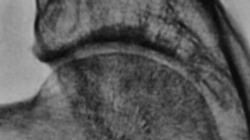

Фрагмент "с увеличением изображения".

Четко определяется деформация бедренной кости в средней трети диафиза, локальное вздутие кости и "перестройка структуры костной ткани".

Представляются фрагменты рентгенограмм "с увеличением изображения"

Имеется искривление диафиза бедра. Если по внутренней поверхности деформация идет за счет "образования", то по наружной поверхности изменений костной структуры нет, отсюда вывод - процесс очень старый, возможно "с младых ногтей", что привело к искривлению еще в период роста. Теперь само образование: участок кистовидного просветления с четкими контурами, гиперостоз, кортикальная пластинка не нарушена, деструкции нет, мягкотканный компонент отсутствует. Образование по крайней мере доброкачественное. Мое мнение - дисплазия. Кроме этого обызвествлены аретрии бедра, что указывает на возраст. Боли в конечности могут быть обусловлены атеросклерозом либо наличием грыжи поясничного отдела позвоночника с корешковым синдромом.

Нейрофиброматоз? Кортикалит?

Валентин Львович, биопсию по-любому надо делать. Диф. ряд прежний: 1. опухоль (злокачественная лимфома (ранее называли ретикулосаркома), ПНЭТ (примитивная нейроэктодермальная опухоль, син. опухоли Юинга), хонросаркома, метастаз); 2. остеомиелит; 3. фиброзная дисплазия. Лично я склоняюсь к лимфоме, хотя диф. ряд большой, можно еще продолжить...